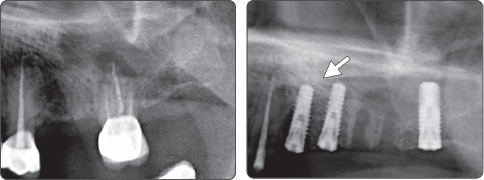

Sequence -Sinus Lift

Only use of Sinus Lift Drill

1. Sinus Lift (Ø4.0 Fixture)

▶ Immediate Implantation and Sinus Lift Technique with Tap Drill (Ø4.0 Fixture)